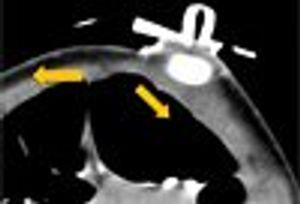

For 3 days, a 7-year-old girl had severe, generalized abdominal pain. The patient described the pain as sharp and achy without radiation; she denied any relieving or aggravating factors. She also reported decreased appetite and energy for the past week.